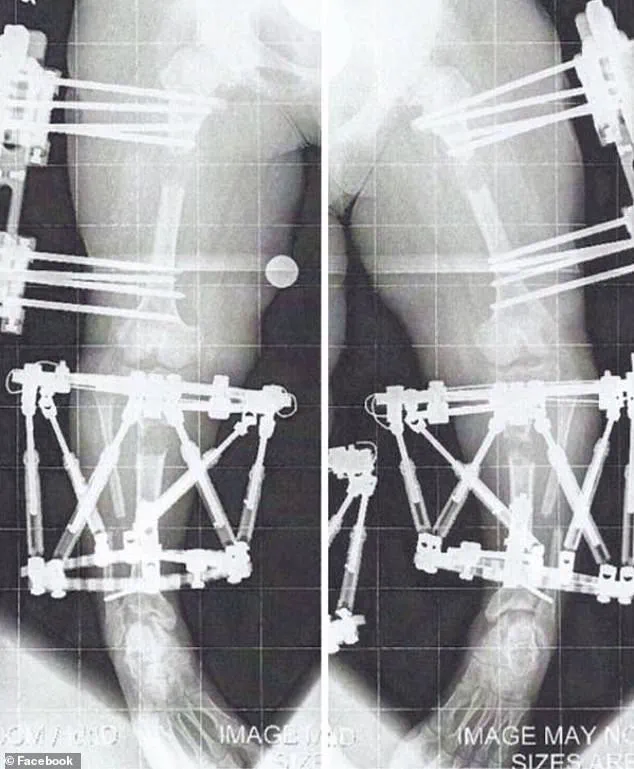

Chandler Crews underwent three limb-lengthening procedures.

Left, at her mature adult height of 3'10'' and, right, at the end of her treatments, standing just over 4'11'' Limb lengthening is controversial in the dwarfism community because it's a painful, expensive, and risky procedure with a high complication rate, and some believe it promotes the idea that short stature is a defect to be 'fixed.' Writing on her website, Crews said: 'I felt like I was never in my own body.

Leg lengthening for dwarfism or bow legs involves surgically cutting the thigh or shin bone and implanting a device (either an external fixator or internal rod) to slowly pull the bone segments apart over several weeks to months.

The process of limb lengthening surgery is a complex and often grueling journey for patients, involving the gradual extension of bones by approximately 1 millimeter per day.

During the 'distraction phase,' the body's natural regenerative capabilities are harnessed as new bone tissue forms in the gap created by the surgical procedure.

Once the desired bone length is achieved, the external or internal fixation devices are removed, and the newly formed bone is given time to fuse and stabilize.

She described her first leg-lengthening procedure as 'months of twists and turns' filled with 'a little blood, sweat, and tears.' The initial recovery phase was particularly demanding, requiring her to attend two to three hours of personal training sessions five days a week, in addition to daily exercises and stretches.

By the time the fixators were removed from her first leg-lengthening surgery in April 2011, the journey was far from over.

Crews had to endure one month of complete weight-bearing restriction, followed by a gradual reintegration of walking.

She recalled using a walker for two weeks, transitioning to two quad canes for a week, and finally walking unassisted by June 2011.

The surgery involved implanting fixators in her humerus, the upper arm bone, and was completed in August 2012 when she was 17 years old.